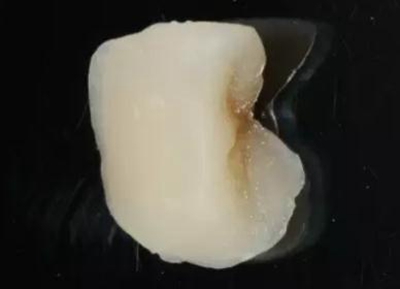

最后附昨天備牙,今日戴牙的一個(gè)美塑嵌體。